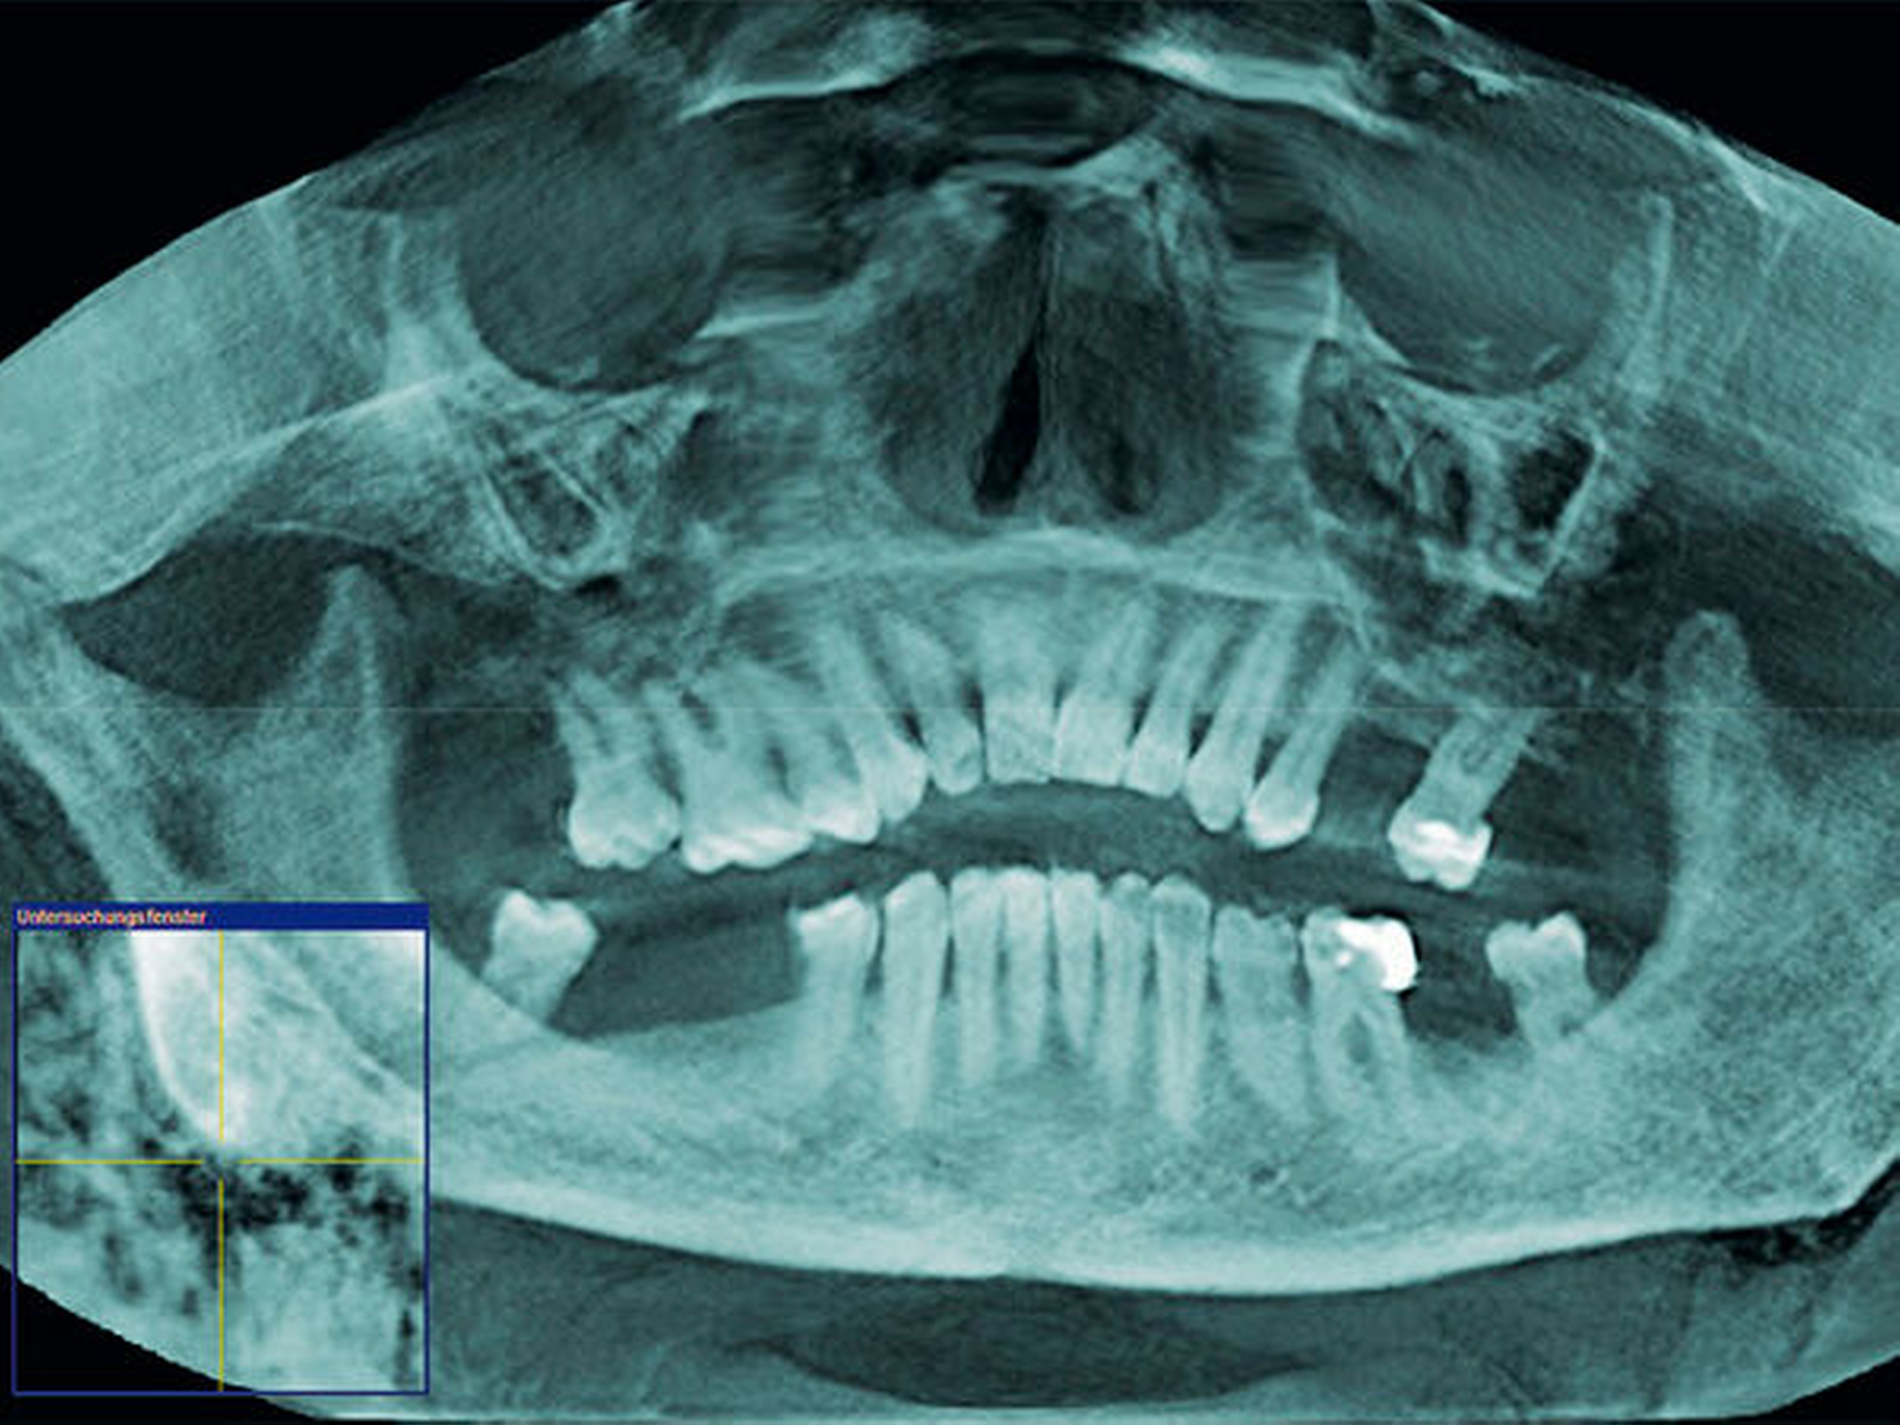

Zum Ausschluss einer Mittelgesichtsfraktur bei palpatorischem Weichteilemphysem erfolgte zur weiteren Diagnostik eine DVT-Aufnahme. Es zeigten sich keine Frakturen im Bereich des Mittelgesichts oder der Kiefer. Jedoch kam in der DVT-Bildgebung sowie in der OPT-Optik ein massives Weichgewebeemphysem zur Darstellung (Abbildungen 2 bis 5).

Weiterhin wird deutlich, dass bei in aller Regel doch sehr eingeschränkter Beurteilbarkeit von Weichgewebe im DVT in diesem speziellen Fall eine weiterführende Diagnostik und Therapie eingeleitet werden konnte.

Das Emphysem war initial im DVT so eindrucksvoll sichtbar, dass es trotz fehlender klinischer Symptomatik im Thoraxbereich, schwieriger Anamnese und blander zweidimensionaler Bildgebung der Lunge (RÖ-Thorax) der Faktor für eine weitere dreidimensionale Bildgebung (CT-Thorax) war, die letztendlich die Verdachtsdiagnose sicherte.

Dass die Diagnosefindung bei unauffälliger OPG- und Röntgen-Thorax-Aufnahme ebenso zeitnah erfolgt wäre, ist eher unwahrscheinlich. So ist anzunehmen, dass bei bestimmten Fragestellungen – wie hier – eine initiale dreidimensionale zahnärztliche Bildgebung mittels DVT dem klassischen OPG überlegen ist.

Zur Frakturdiagnostik im Mittelgesichtsbereich eignet sich das DVT sehr gut, außerdem ist die freie Luft des Emphysems im undifferenzierten Weichgewebe gut darstellbar.

Mittels der digitalen Volumentomografie können Weichteile schlecht bis gar nicht beurteilt werden, Lufteinschlüsse im Weichgewebe hingegen können gut dargestellt werden.